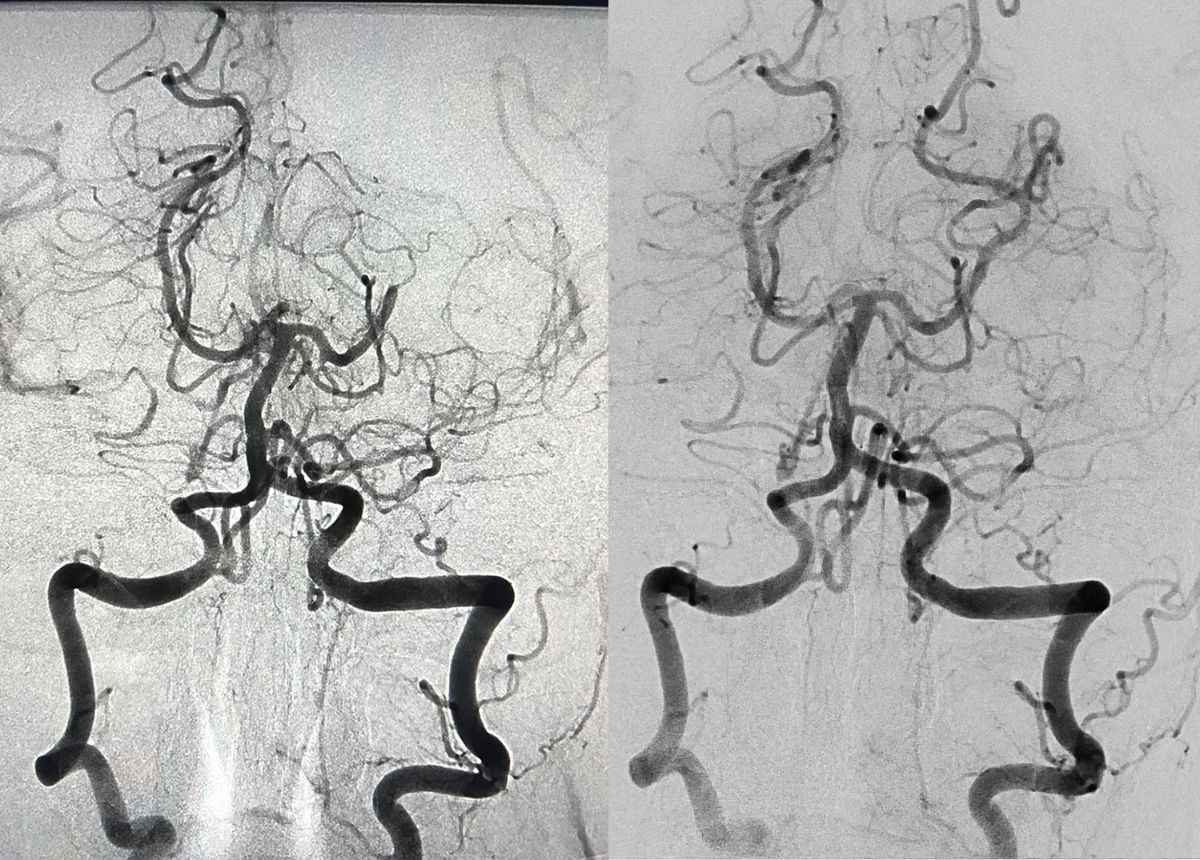

Auf diesen Angiografie-Bildern sieht man die hintere Gehirnarterie: vor (links) und nach der Entfernung eines Gerinnsels (rechts).